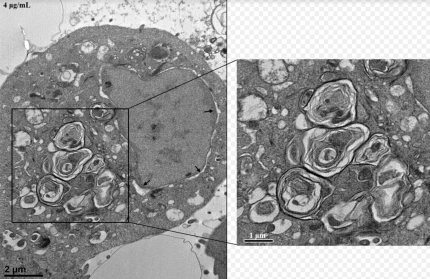

이 DDAC를 연구한 결과 4μg/mL의 농도에서

세포 생존율을 급격히 감소시키고

세포 내 소기관 손상과 함께

세포 자살과 세포막 손상을 유도한다고 하는데

그리고 이 DDAC에 노출된 쥐와 세포에서는

라멜라 구조체가 형성되었고 이온을 함유하는

용액 내에서 그 구조가 뚜렷이 변화됐다고 합니다.

이 라멜라 구조체의 형성은 DDAC의 체내 축적

가능성을 높이는 결과를 가져와

DDAC에 반복적으로 노출되면 결국

폐 질환으로 이어질 수 있다고 합니다.